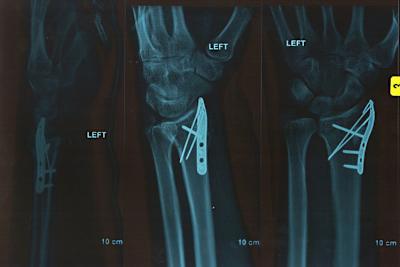

Nach guten Leistungen bei den Wintertestfahrten erwarten der Waliser und das Team ParkinGO MTC Aprilia viel für den Saisonauftakt in Australien. Doch Davies zog sich in einem schnellen Streckenabschnitt in der zweiten Qualifikationssession einen Bruch des linken Handgelenkes und der Elle zu. Inzwischen geht es ihm besser.

"Es geht mir gut, in den paar Wochen habe ich echte Fortschritte gemacht", sagt der Aprilia-Fahrer. "Ich bin ziemlich glücklich und kann nicht mehr verlangen. Mein Handgelenk schmerzt und ist geschwollen, aber es befindet sich in etwa im Heilungs-Zeitplan. Die Ärzte haben mich mit einem abnehmbaren Gips ausgerüstet, dieser wurde vor ein paar Tagen entfernt. Ich kann mein Handgelenk nun wieder bewegen, und die Knochen beginnen zusammenzuwachsen. Mein Daumen scheint noch nicht allzu viel tun zu wollen, aber auch er wird immer besser." Davies erlitt erhebliche Verletzungen, die eine sofortige Behandlung erforderten. Er wurde in Melbourne operiert: "Mein Ellen-Knochen war leicht verschoben und gebrochen, also hatte er sich ein wenig geöffnet. Die Chirurgen renkten ihn wieder ein und befestigten drei Schrauben daran, eine lange und zwei kurze durch den Radius, inklusive einer kleinen Platte. Um richtigen Halt zu gewährleisten, setzten sie dazu noch ein künstliches Knochentransplantat ein. Zwei Drähte wurden eingesetzt, um die Platte an einem anderen Teil des Armes zu halten. An der gebrochenen Elle war keine Arbeit nötig, dieser Bruch kann natürlich heilen." "Der Fortschritt ist gut, ich sehe keinen Grund, warum ich in Imola nicht fahren sollte", bekräftigte Chaz. "Bisher sind wir auf dem richtigen Weg. Ich werde wahrscheinlich nicht zu 100 Prozent fit sein und Schmerzen haben. Aber ich sollte zu 80 oder 90 Prozent fit sein. Dass die Lücken zwischen den Rennen so gross ist, ist für mich wirklich Glück, grosses Glück."